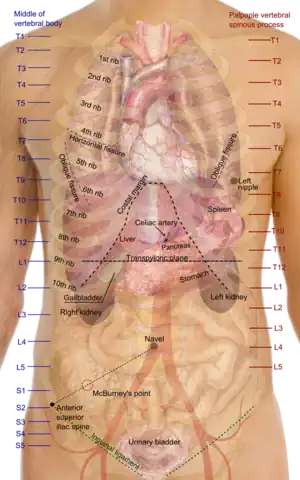

Individual vertebrae are named according to their corresponding body region (neck, thorax, abdomen, pelvis or tail). In clinical medicine, features on vertebrae (particularly the spinous process) can be used as surface landmarks to guide medical procedures such as lumbar punctures and spinal anesthesia. There are also many different spinal diseases in humans that can affect both the bony vertebrae and the intervertebral discs, with kyphosis/scoliosis, ankylosing spondylitis, degenerative discs and spina bifida being recognizable examples.

Individual vertebrae of the human vertebral column can be felt and used as surface anatomy, with reference points are taken from the middle of the vertebral body. This provides anatomical landmarks that can be used to guide procedures such as a lumbar puncture and also as vertical reference points to describe the locations of other parts of human anatomy, such as the positions of organs.